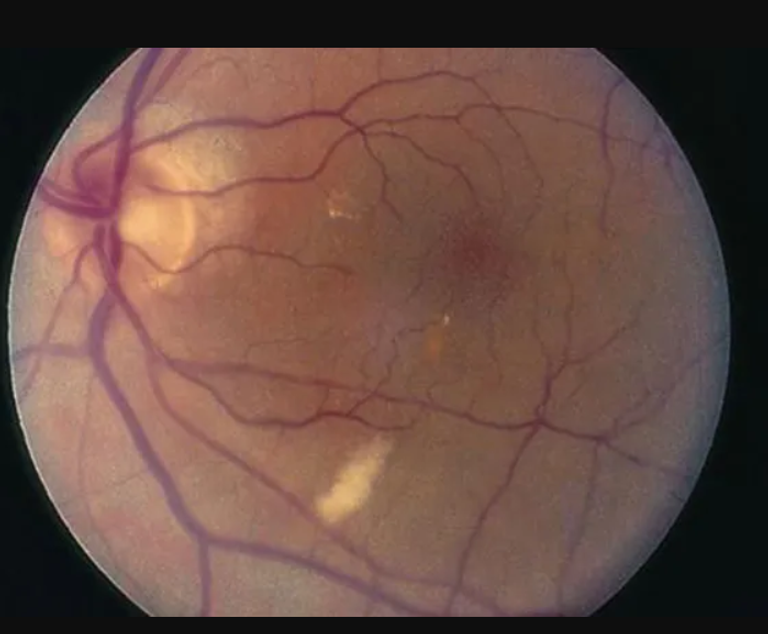

وأجرى فريق البحث هذه الفحوصات باستخدام كاميرا تصور الشبكية دون اتساع حدقة العين، وكشفت هذه الفحوصات عن بقع بيضاء على شبكية العين في 11٪ من الحالات.

وتُعرف هذه البقع باسم بقع الصوف القطني، وهي علامات على معاناة شبكية ثانوية لانسداد الشريان الصغير، وويمكن أن تكون ناجمة عن انسداد أو التهاب في الأوعية الشبكية، حيث يؤدي التهاب الأوعية الدموية إلى إعاقة الدورة الدموية وربما نقص الأكسجين.